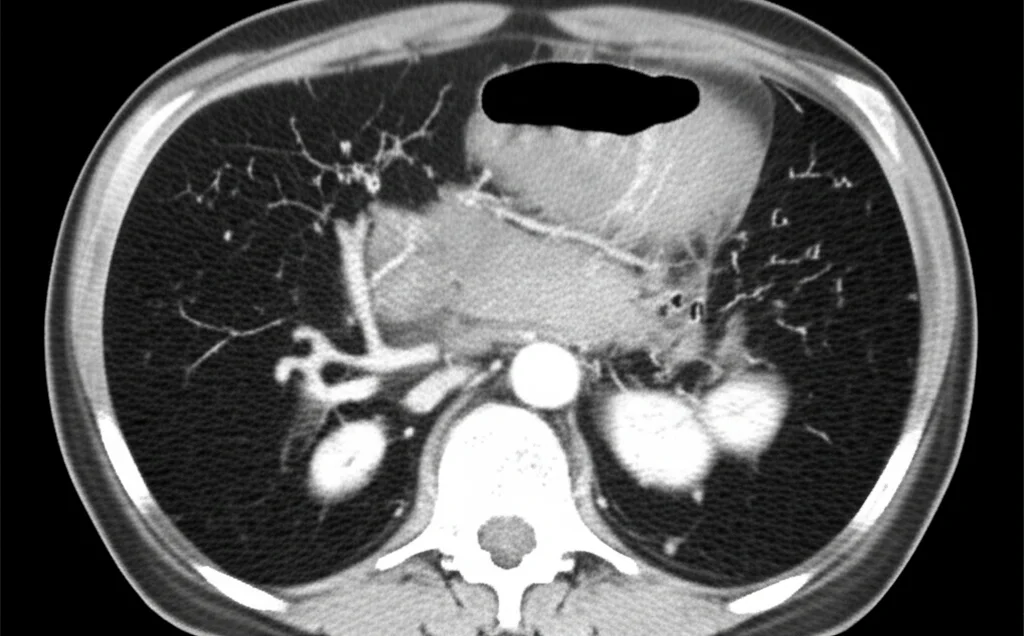

Ed è qui che entra in gioco uno studio interessante, condotto retrospettivamente su 160 pazienti trattati con ESWL per calcoli pancreatici tra il 2017 e il 2023 presso il First People’s Hospital di Hangzhou. L’obiettivo era proprio capire quali fattori potessero predire l’esito della litotrissia. I ricercatori hanno raccolto un sacco di dati: età, sesso, se era stato messo uno stent nel dotto pancreatico prima dell’ESWL, e soprattutto, grazie alla TC spirale addominale, hanno misurato il valore massimo di densità dei calcoli (espresso in unità Hounsfield, HU) e il loro volume totale (usando un software specifico, ITK-SNAP).